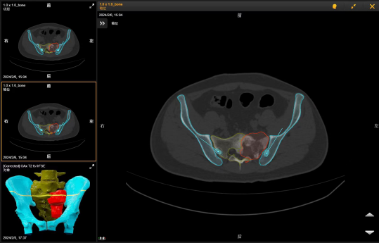

术前,通过对肿瘤的核磁和CT图像进行融合显像,让术者对肿瘤的范围进行3D立体化的了解,医生根据图像信息,制定切除的路径和切除范围,确定详细的术前规划。

“O”型臂导航系统是一种先进的骨科手术辅助设备,能精准定位肿瘤。该系统由“O”型臂术中影像和手术导航系统组成,在骨科手术中发挥着重要作用,为手术医生实时提供术中3D立体三维影像,使得手术医生的视角更广,帮助医生避开周围重要的血管和神经,精准定位病变部位和范围,确保了肿瘤的完整切除和正常骨质的最大程度保留,大大提高了手术的安全性。

精准切除肿瘤后,借助骨肿瘤科自主研发的3D打印组合式半侧骶骨假体进行重建。并在O臂导航系统的引导下,精确放置假体和螺钉,进一步提升患者的重建效果。此外,该系统还可以缩短手术时间,加快患者的康复。